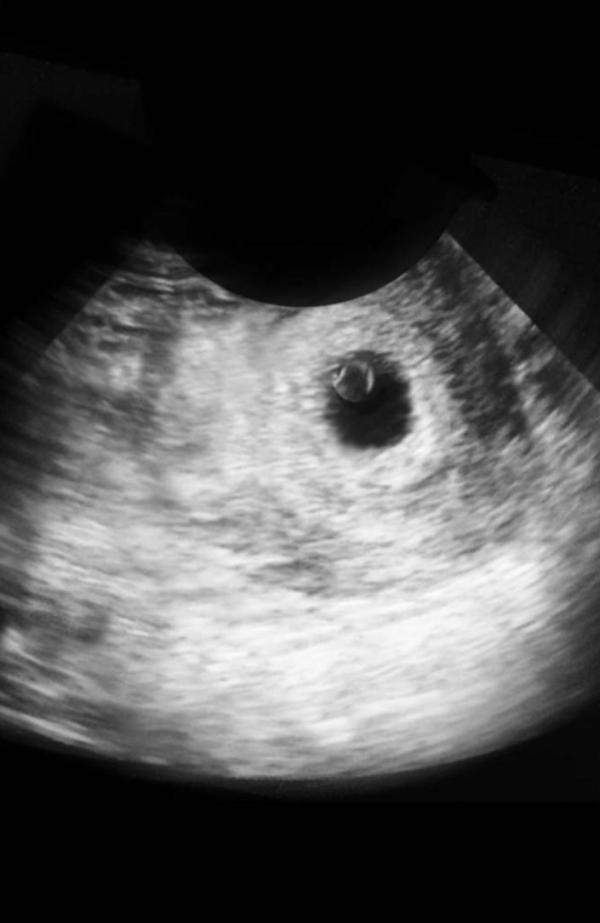

Не только хгч не радует. Сделала узи, трансвагинальное. По месячным 5 недель, на узи увидели плодное яйцо с желточным мешочком. Размер яйца 0,56 см. Узист говорит остает по сроку, сделать следующее узи через 10-14 дней. Сегодня 26 дпо. Хгч последние: 20 дпо 757, вчера 25 дпо 3430. Чуть больше нижних границ по таблицам. Не знаю что и ожидать…Фото второе из инета, но так было и на экране сегодня

С сыном в 5.4 был эмбрион 2 мм, пя 8 мм и жм 1,8